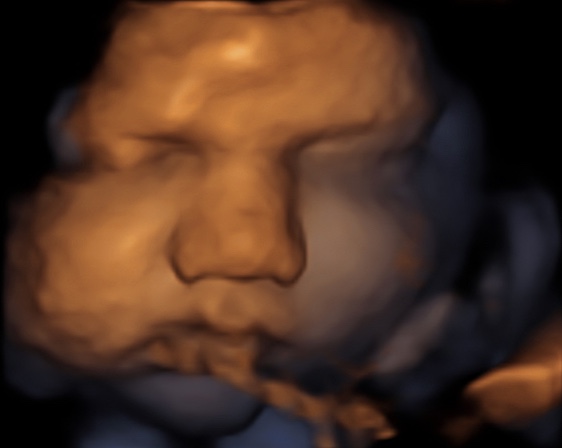

39 weken

Een echo na 39 weken.